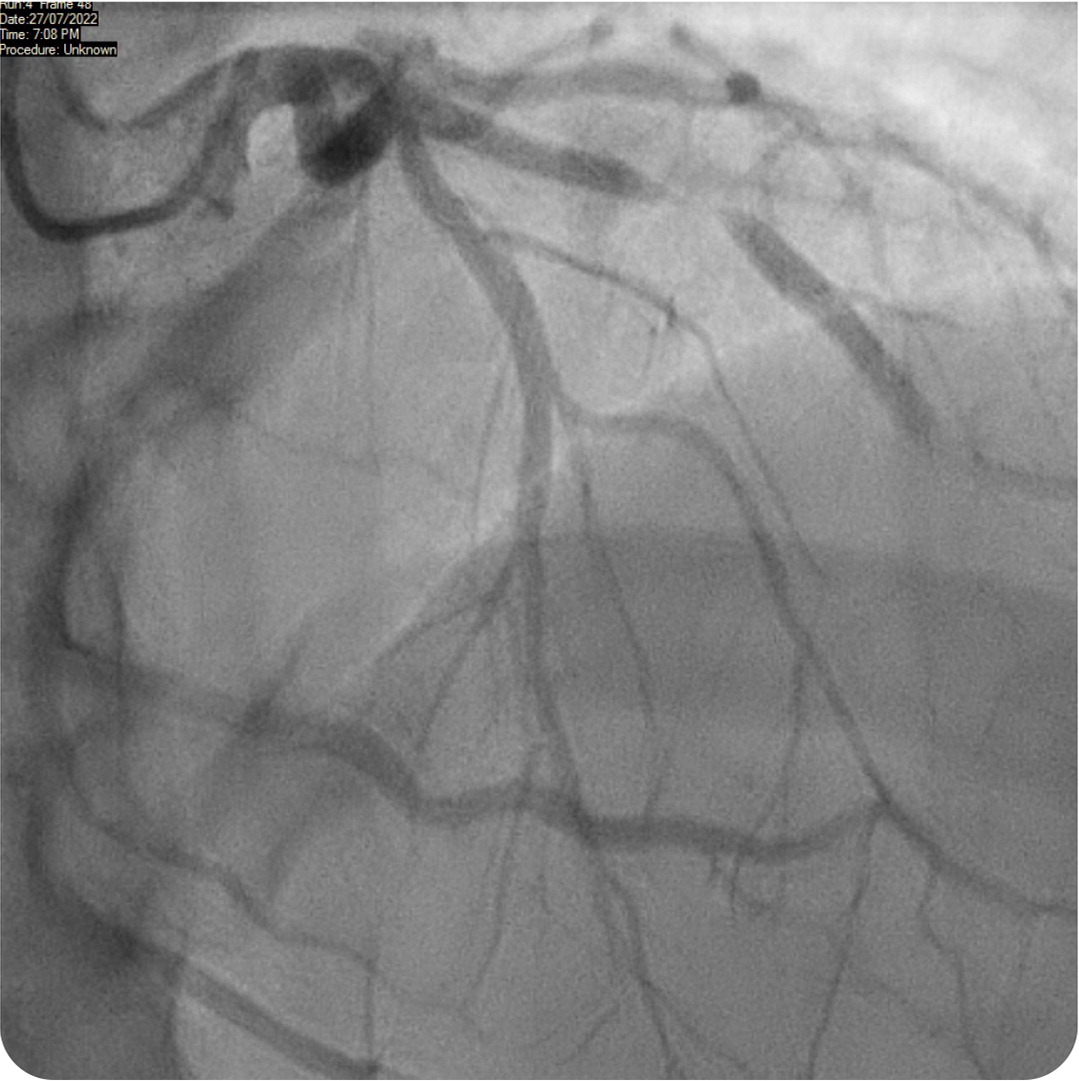

The answer is E: Wellens syndrome, defined by deeply inverted or biphasic T waves in leads V2 and V3 that are highly specific for critical stenosis of the left anterior descending coronary artery 2 (Figure 2). This patient had the typical presentation of Wellens syndrome, with episodes of intermittent chest pain caused by sudden occlusion of a previously stenotic coronary artery.3 These episodes are not usually captured by electrocardiography. Reperfusion of the left anterior descending coronary artery by spontaneous clot lysis resolves the chest pain but causes T waves to become biphasic in the corresponding V2 and V3 leads.4

These episodes also feature an isoelectric or minimally elevated ST segment (less than 1 mm), preserved precordial R-wave progression, and a lack of precordial Q waves. Patients have normal or minimally elevated serum troponin levels. This patient was transferred to the emergency department, where repeated electrocardiography showed persistent T-wave changes. Initial troponin levels were normal (34 ng per L [34 mcg per L]), with subsequent measurement showing mild elevation (95 ng per L [95 mcg per L]). Twelve hours later, he underwent percutaneous coronary angioplasty, which revealed 95% stenosis of the proximal left anterior descending coronary artery (Figure 2). The patient was treated with a drug-eluting stent (Figure 3), and subsequent echocardiography showed preserved ejection fraction.